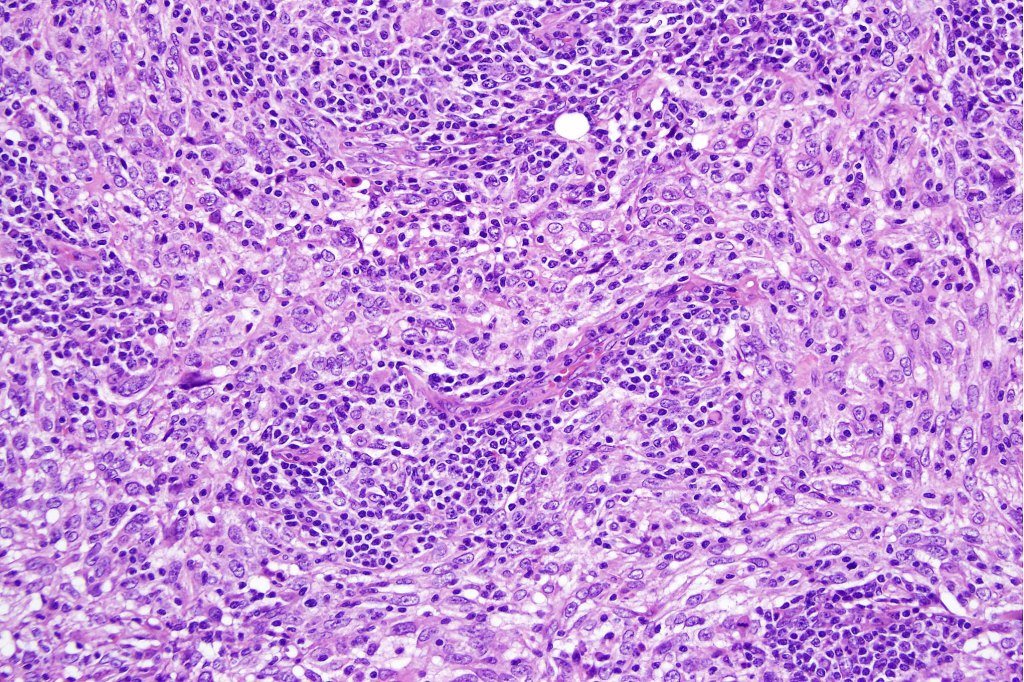

•Dermal generally circumscribed tumor nodule (less often it may show an infiltrative border)

•Syncytial epithelial component in nests, cords or sheets surrounded by an intense lymphoplasmacytic infiltrate

•Epithelial cells are large with abundant cytoplasm and vesicular nuclei with conspicuous nucleoli

•Marked mitotic activity, variable pleomorphism

•Absence of an epidermal connection